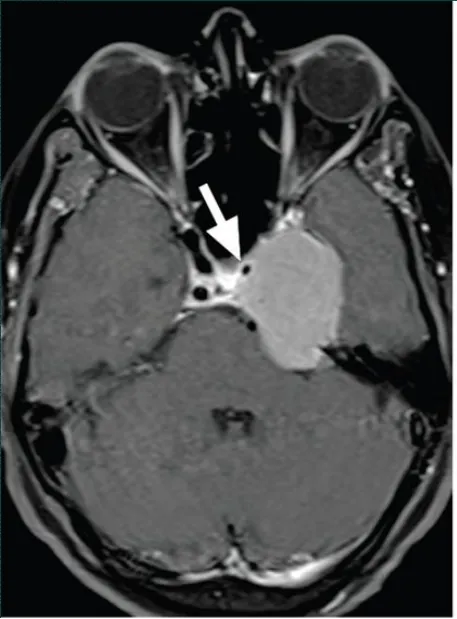

術(shù)后一周復查磁共振增強,術(shù)區(qū)高信號為暫時未吸收的止血材料等

(術(shù)后一周復查磁共振增強,術(shù)區(qū)高信號為暫時未吸收的止血材料等)